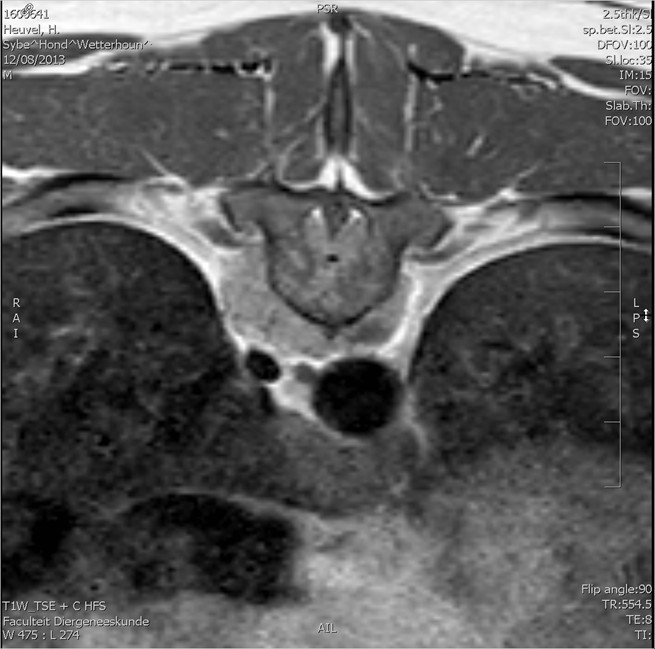

Het noodlot: Helaas sloeg in januari het noodlot toe. Hij was een week wat rustiger dan normaal maar ik dacht dat de hormonen begonnen op te spelen door een loopse hond in de buurt. Hij at ook slechter gedurende die week totdat ik er achter kwam dat hij pijn had en niet goed vanaf de grond kon eten. Dus op vrijdag naar de dierenarts, hij liep- en stond toen ook een beetje raar. De dierenarts dacht aan een blessure en schreef rust en pijnstilling voor. Sybe was zo gespierd dat het niet iets chronisch kon zijn. Gedurende het weekend ging Sybe steeds slechter lopen, hij zwalkte met zijn achterlijf heen en weer en zakte af en toe door een achterpoot. Nog 2 maal een dierenarts gezien dat weekend en op maandag weer terug naar onze eigen dierenarts. Die zorgde ervoor dat we in Utrecht met spoed bij Neurologie terecht konden voor een MRI scan. Sybe kon toen al helemaal niet meer lopen en had geen enkele controle over de achterpoten. Omdat er zowel een probleem in de nek als in de rug zat zou er van beide gebieden een scan gemaakt worden, die ieder 1½uur zouden duren. Iedereen dacht eigenlijk aan een hernia. Na 1uur kwam hij al weer terug van de MRI. De diagnose was niet best, een bottumor in een ruggenwervel, inoperabel met waarschijnlijk al uitzaaiingen in de buik. We konden hem gelijk laten inslapen, hij was toch nog onder narcose, zeiden ze. Op dat moment staat je wereld stil. Hoe kon dit waar zijn! Dit is het laatste wat je verwacht, zo’n prachtige jonge hond, pas 2 jaar en 5 maanden oud, waar je nog zoveel mooie plannen mee had. Die naar mijn idee nog net niet helemaal volwassen was maar zo goed op weg was een fantastische volwassen hond te worden. Op mijn vraag of dat vaker voorkwam en of er wat over bekend is bij dit ras, zeiden ze dat ze dit niet vaak zagen en zeker niet bij zulke jonge honden. Dit was pure pech.